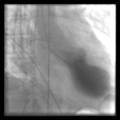

Left ventriculogram during systole displaying the characteristic apical ballooning with apical motionlessness in a patient with takotsubo cardiomyopathy

- تصوير الوعاء التاجي: خلال تصوير الأوعية التاجية، يتم حقن نوع من الصبغة – التي يكتشفها جهاز تصوير الأشعة السينية – في الأوعية الدموية بالقلب. ثم بعد ذلك يأخذ جهاز الأشعة السينية سلسلة من الصور (تصوير الأوعية) مما يعطي طبيبك رؤية مفصلة داخل أوعيتك الدموية. عادة لا يوجد لدى الأشخاص المصابين بمتلازمة القلب المنكسر انسداد في الأوعية الدموية، بينما يعاني الأشخاص المصابون بأزمة قلبية دائمًا بانسداد يظهر مرئيًا في تصوير الأوعية.